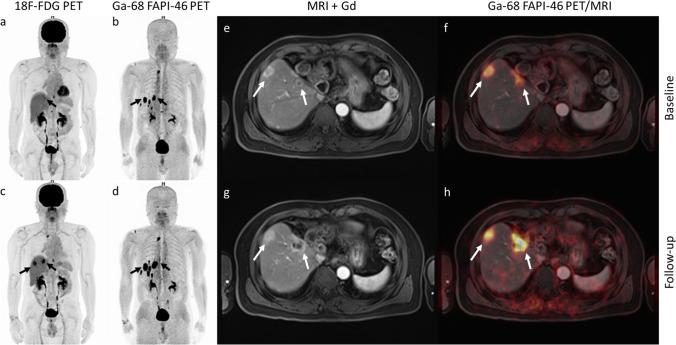

The 27 patients had a median age of 68 years (interquartile range: 60-74 years; 21 men). Primary intrahepatic tumours were reported in 13 patients (15 imaging studies) with cholangiocarcinoma (CCA) and in 14 patients with hepatocellular carcinoma (HCC). All intrahepatic lesions detectable on MRI were also detected on [ Ga]Ga-FAPI-46 PET/CT giving a sensitivity of 100% (19/19), whereas the sensitivity of [F]FDG PET/CT was 58% (11/19). All intrahepatic lesions were detected on [ Ga]Ga-FAPI-46 PET/CT, on which they showed higher activity (median SUVmax: 15.61 vs. 5.17; P < .001) and higher target-to-background ratio (TBR; median, 15.90 vs. 1.69, P < .001) than on [F]FDG, especially in patients with CCA (median TBR, 21.08 vs. 1.47, respectively; P < .001). The uptake positivity rate in regional node metastasis was 100% (12/12) on [ Ga]Ga-FAPI-46 PET/CT compared with 58% (7/12) on [F]FDG PET/CT. All patients with distant metastasis (100%, 14/14) were detected on both [F]FDG and [ Ga]Ga-FAPI-46 PET/CT imaging, although more distant metastatic lesions were detected on [ Ga]Ga-FAPI-46 PET/CT than on [F]FDG (96% (42/44) vs. 89% (39/44), respectively).

27 例患者的中位年龄为 68 岁(四分位距:60-74 岁;21 例男性)。13 例患者(15 项影像学研究)报告原发性肝内肿瘤为胆管细胞癌(CCA),14 例患者为肝细胞癌(HCC)。MRI 上可检测到的所有肝内病变在 [68Ga]Ga-FAPI-46 PET/CT 上也均有检出,其灵敏度为 100%(19/19),而 [F]FDG PET/CT 的灵敏度为 58%(19/19)。所有肝内病变在 [68Ga]Ga-FAPI-46 PET/CT 上均有检出,在该检查中它们显示出更高的活性(中位 SUVmax:15.61 比 5.17;P<0.001)和更高的靶-背景比(TBR;中位数,15.90 比 1.69,P<0.001),尤其是在 CCA 患者中(中位 TBR,分别为 21.08 比 1.47;P<0.001)。在区域淋巴结转移中,[68Ga]Ga-FAPI-46 PET/CT 的摄取阳性率为 100%(12/12),而 [F]FDG PET/CT 的摄取阳性率为 58%(7/12)。所有远处转移患者(100%,14/14)在 [F]FDG 和 [68Ga]Ga-FAPI-46 PET/CT 成像上均有检出,尽管 [68Ga]Ga-FAPI-46 PET/CT 比 [F]FDG 检测到更多的远处转移病灶(96%(42/44)比 89%(39/44))。